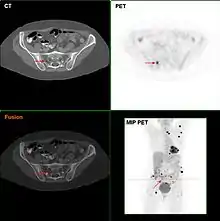

Metastatic melanomas can be detected by X-rays, CT scans, MRIs, PET and PET/CTs, ultrasound, LDH testing and photoacoustic detection.[90] However, there is lack of evidence in the accuracy of staging of people with melanoma with various imaging methods.[91]

It is common for patients diagnosed with melanoma to have chest X-rays and an LDH test, and in some cases CT, MRI, and/or PET scans. Although controversial, sentinel lymph node biopsies and examination of the lymph nodes are also performed in patients to assess spread to the lymph nodes. A diagnosis of melanoma is supported by the presence of the S-100 protein marker.